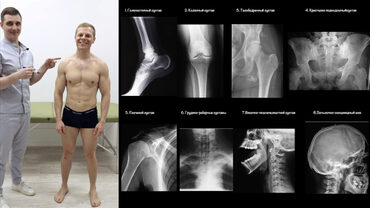

В этом маленьком видео-уроке Кирилл расскажет что же такое паттерн шага, и как он складывается. Расскажет какие суставы участвуют в шаге, наглядно покажет и нарисует их на модели. С помощью мануально-мышечного тестирования проверит оба шага, а также вы узнаете как диагностировать и искать регионы приводящие к дисфункциям.